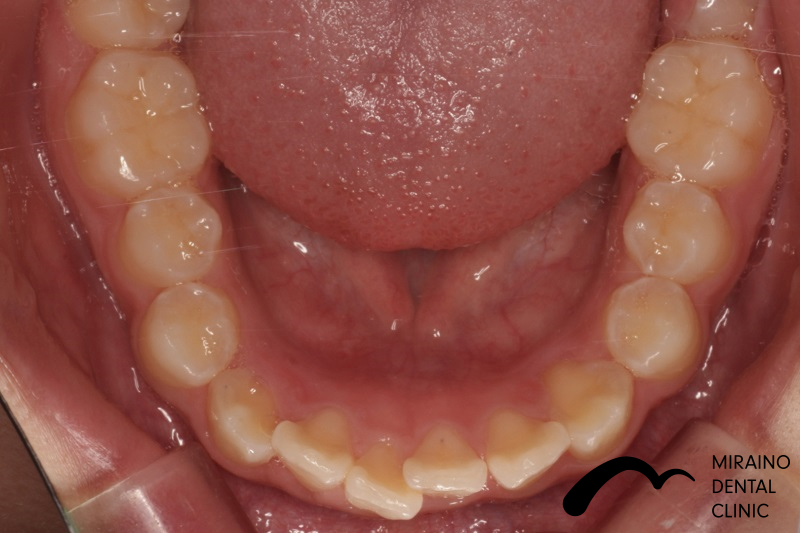

叢生(ガチャガチャ・ガチャ歯)②

| 施術名 | マウスピース矯正(インビザライン) |

| 施術の内容 | 歯科矯正でも目立ちにくい新しい矯正方法です。 透明に近いマウスピース型の矯正装置(アライナー)のため、歯に装着しても目立つことなく歯並びを矯正することが出来ます。 また、一人ひとりの合わせて矯正装置を作製いたします |

| 治療費 | インビザライン990,000円 |

| 考えられるリスク、副作用 | 疼痛・咬合時痛を生じる事があります。時間経過とともに治ります。 |

| 考えられるリスク、副作用[矯正] | 継続使用により緩んだり、外れやすくなる事があります。 割れたり壊れたりする事があります。 諸々の事情により、治療期間が当初よりも伸びる事があります。 所定の装着時間22時間を守って頂けない場合、治療計画どおりに治らない可能性があります。 歯が動く際に、痛みが出る事があります。 矯正期間中は虫歯や歯周病のリスクが高まりますので、しっかりとしたケアが必要です。 歯の移動に伴う歯肉退縮や歯根吸収が起こる事があります。 インビザライン・システム(invisalignR)は、アメリカのアラインテクノロジー社より提供されている、カスタムメイドの矯正装置ならびに、これを用いた治療システムを指します。 インビザラインを用いた治療は保険適用外の自由診療となります。 厚労省の認可(医薬品医療機器等法上の承認)は得ていないため、まだ明らかになっていないリスクが存在する可能性があることをご了承ください。 |

| 全て | 必ずしもご希望通りの見た目にならない事があります。 |